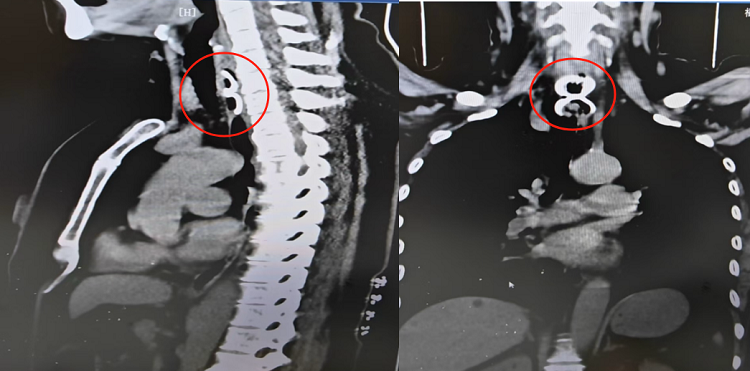

国产自拍av 耳鼻咽喉科林清花主治医师迅速检查咽部、喉部均未发现异物后,立即安排患者行胸部CT检查,提示食管上段见条片状致密影,长约3.5cm。

为进一步诊治,林清花医生立即将患者转往消化内镜中心。消化内镜中心林芬副主任医师根据张大妈病史和检查结果,高度怀疑花蛤嵌顿在食管入口处,花蛤壳边缘锐利,取出过程中极有可能造成食管的二次划伤,甚至脱落滑入气管,增加危险。随即林芬副主任医师联系了麻醉科协同会诊。

多科室协同下,林芬副主任医师执镜操作,当胃镜进入食道,只见一个花蛤嵌顿于食道上段。手术过程比想象得更加困难,稍有不慎边缘锐利的花蛤壳就可能会划破脆弱的食道,造成食道出血、穿孔。林芬副主任医师小心翼翼用异物钳钳持花蛤的一端,通过异物钳调整花蛤方向后,快速、精准的将花蛤壳取出。仅用时大约2分钟,最终卡在张大妈食管处、长达2.3厘米边缘锋利的完整花蛤被取出来了!林芬副主任医师再次进镜观察,手术过程顺利,未造成食道损伤。手术结束后,患者家属对消化内镜中心、麻醉医护团队的高超技术及勇于担当的精神深表感激。